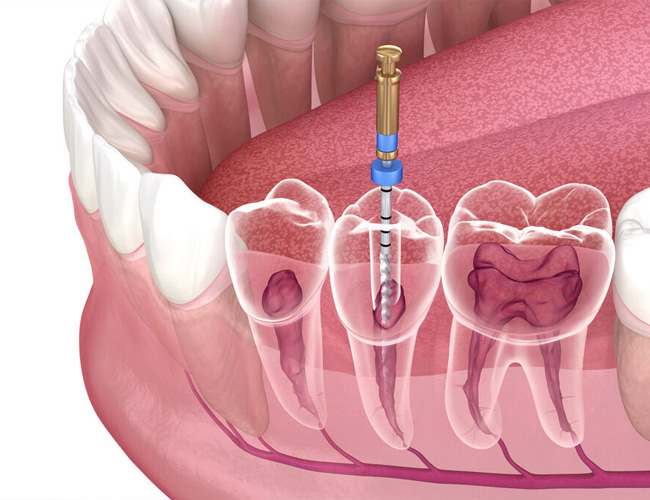

Endodoncia, známa aj ako ošetrenie koreňových kanálikov, je zákrok, ktorého cieľom je zachrániť zub, ktorý by inak musel byť odstránený. Vnútri každého zubu sa nachádza dreň – mäkké tkanivo obsahujúce nervy a cievy. Keď sa táto dreň zapáli alebo infikuje (napríklad v dôsledku hlbokého kazu alebo úrazu), zub začne bolieť a jeho stav sa môže zhoršovať. Endodoncia odstraňuje postihnutú dreň, dezinfikuje vnútro zubu a následne ho uzatvára, čím zub zachraňuje a umožňuje mu ďalej fungovať.

1. Diagnostika a príprava – Lekár urobí röntgenový snímok, aby zistil rozsah poškodenia. Následne podá lokálnu anestéziu, aby bol zákrok bezbolestný. 2. Odstránenie infekcie – Lekár otvorí zub a vyčistí koreňové kanáliky od infikovanej drene. 3. Dezinfekcia a vyplnenie – Priestor vo vnútri zubu sa dôkladne dezinfikuje a vyplní špeciálnym materiálom, ktorý zabraňuje ďalšej infekcii. 4. Obnova zubu – Po endodontickom ošetrení môže zub potrebovať výplň alebo korunku, aby získal späť svoju pevnosť a funkčnosť.